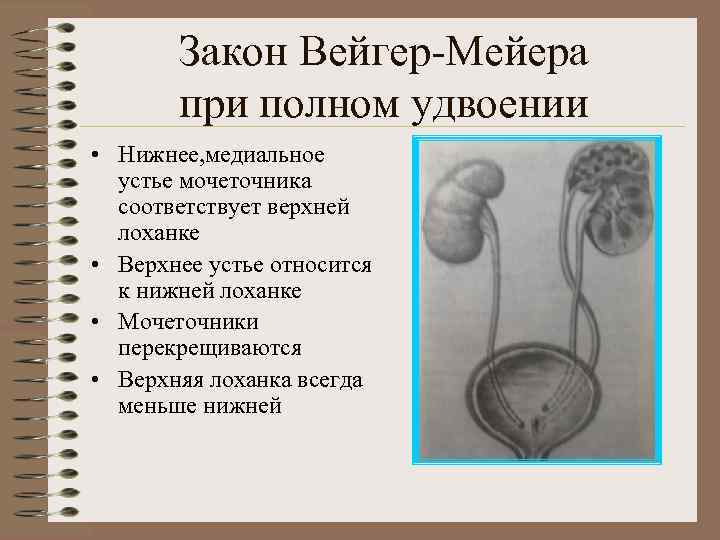

Закон Вейгер-Мейера при полном удвоении • Нижнее, медиальное устье мочеточника соответствует верхней лоханке • Верхнее устье относится к нижней лоханке • Мочеточники перекрещиваются • Верхняя лоханка всегда меньше нижней